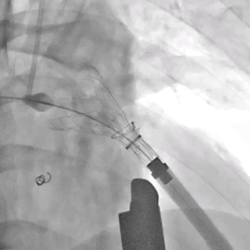

手术由心脏大血管外科周诚教授主刀,钟禹成教授、李庚教授精准定位,予患者行肺动脉环缩塑形后,在心导管造影和食道心超的双重精确引导下,经由右心室表面穿刺准确地将32#介入肺动脉瓣放置到肺动脉的预定位置,术后TEE提示肺动脉瓣植入位置理想、固定良好,无瓣周漏或中央反流,手术效果满意。

肺动脉瓣释放